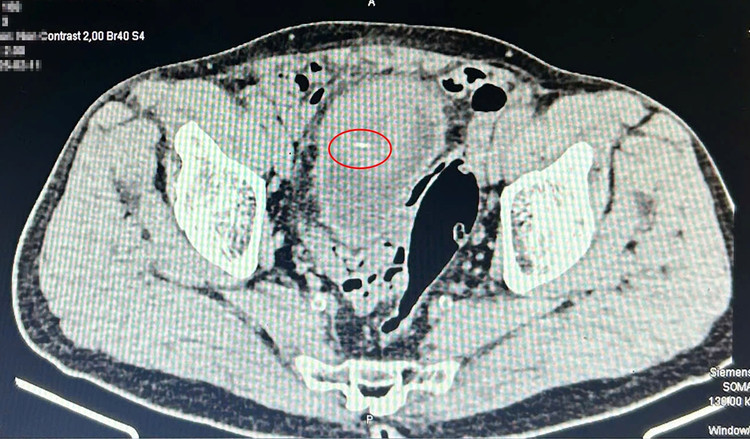

Trường hợp đầu tiên là bệnh nhân V.Đ.C (77 tuổi, ở thị trấn Cái Rồng, huyện Vân Đồn), nhập viện trong tình trạng tiểu khó, đau tức vùng hạ vị kéo dài nhưng không rõ nguyên nhân. Ban đầu, người bệnh chỉ nghĩ rằng mình mắc bệnh lý tiết niệu thông thường. Tuy nhiên, qua siêu âm và chụp cắt lớp vi tính, các bác sĩ phát hiện một khối áp xe ở thành trên bàng quang, bên trong có một dị vật dài, nhọn, nghi là xương cá.

| Hình ảnh chụp cắt lớp dị vật nhọn trong bàng quang của bệnh nhân C - Ảnh BVCC |

Kíp mổ khoa Ngoại tiến hành nội soi kiểm tra thấy khối áp xe kích thước 5x6cm đẩy lồi vào trong gây áp xe thành bàng quang. Mở nhỏ bóc gọn khối áp xe ra ngoài và khâu phục hồi bàng quang. Cắt khối áp xe thấy dị vật bên trong là mảnh xương sắc nhọn, dài khoảng 5cm.